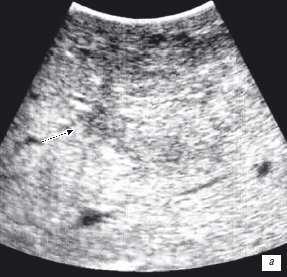

Клинический пример N2. Пациентка Р. находилась на лечении в ГУРОНЦ РАМН. При прохождении обследования был установлен диагноз рак толстой кишки. По данным ультразвуковой компьютерной томографии на фоне выраженной диффузной неоднородности паренхимы печени очаговые образования не определялись. При проведении ангиографии и компьютерной томографии так же убедительных данных за наличие метастазов в печень получено не было. При интраоперационном ультразвуковом исследовании были выявлены два очага, характерными особенностями которых являлись малые размеры (0,2 - 0,4 см), а так же нечеткость контуров и изоэхогенность структуры (рис. 1 а,б).

Рис. 1. Метастатические очаги (стрелки) в печени при интраоперационной ультразвуковой томографии.